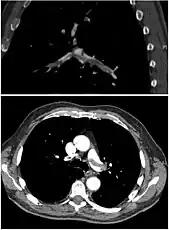

CT angiography

CT pulmonary angiography (CTPA) is a pulmonary angiogram obtained using computed tomography (CT) with radiocontrast rather than right heart catheterization. Its advantages are that it is accurate, it is non-invasive, it is more often available, and it may identifying other lung disorders in case there is no pulmonary embolism. The accuracy and non-invasive nature of CTPA also make it advantageous for people who are pregnant.[52]

Assessing the accuracy of CT pulmonary angiography is hindered by the rapid changes in the number of rows of detectors available in multidetector CT (MDCT) machines.[53] According to a cohort study, single-slice spiral CT may help diagnose detection among people with suspected pulmonary embolism.[54] In this study, the sensitivity was 69% and specificity was 84%. In this study which had a prevalence of detection was 32%, the positive predictive value of 67.0% and negative predictive value of 85.2%. However, this study's results may be biased due to possible incorporation bias, since the CT scan was the final diagnostic tool in people with pulmonary embolism. The authors noted that a negative single slice CT scan is insufficient to rule out pulmonary embolism on its own. A separate study with a mixture of 4 slice and 16 slice scanners reported a sensitivity of 83% and a specificity of 96%, which means that it is a good test for ruling out a pulmonary embolism if it is not seen on imaging and that it is very good at confirming a pulmonary embolism is present if it is seen. This study noted that additional testing is necessary when the clinical probability is inconsistent with the imaging results.[55] CTPA is non-inferior to VQ scanning, and identifies more emboli (without necessarily improving the outcome) compared to VQ scanning.[56]